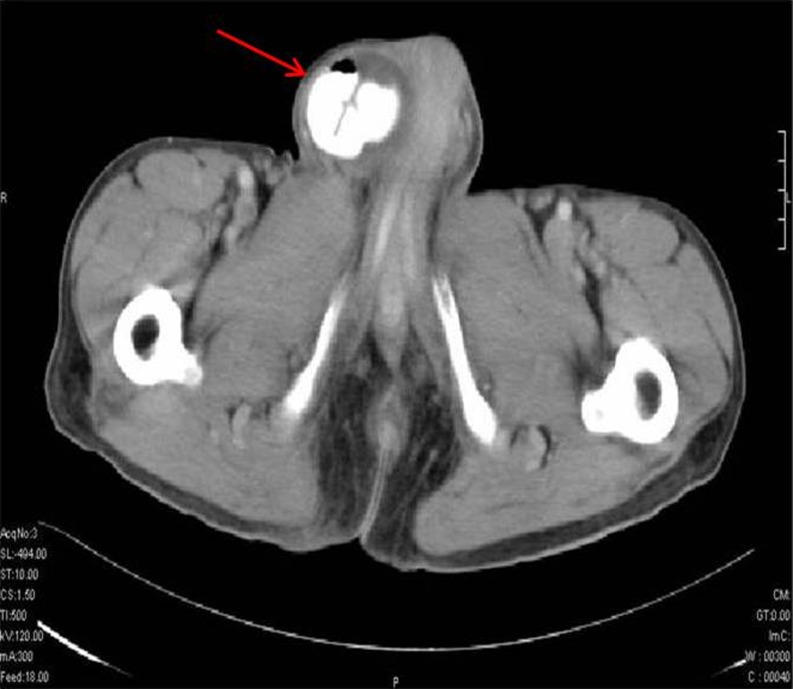

Direct inguinal hernia almost always occurs in the middle aged and elderly because their abdominal wall weakens as they age. Direct inguinal hernias (Fig. 2) are located medial to the inferior epigastric artery and are due to the defects in the fascia transversalis and conjoint tendon which forms the posterior wall of the inguinal canal. It rarely extends into the scrotum.

Fig. 2.

Direct inguinal hernia. CT scan shows bilateral hernial sacs in the inguinal region. The hernial sac is located medial to the epigastric vessels (arrow)